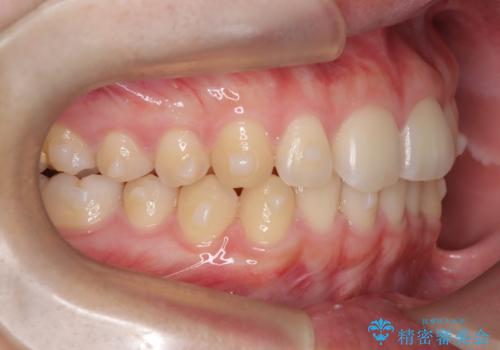

前歯のガタツキを改善する治療法として、マウスピース矯正が適していることが多いです。

マウスピース矯正は、金属製のブラケットやワイヤーを使用せずに、透明なマウスピースを装着して歯を移動させる方法です。そのため、目立たず、痛みも少ないです。